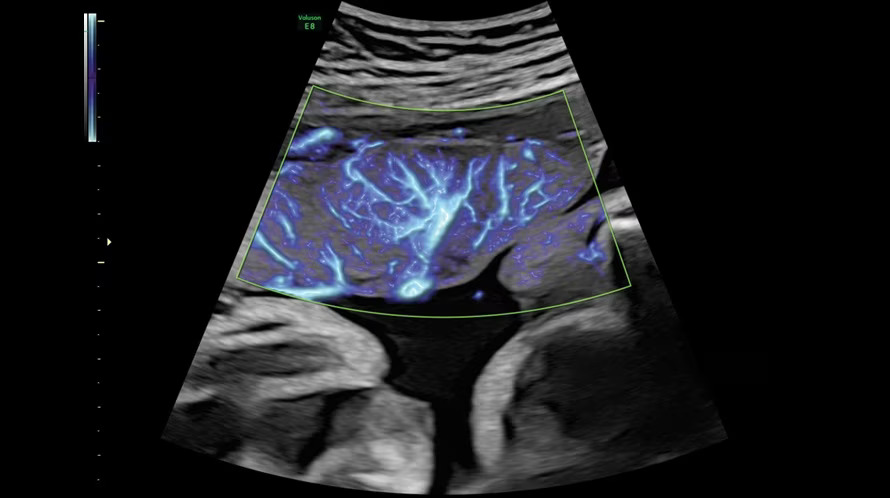

Radiantflow - новое поколение цветового допплера Radiantflow упрощает и ускоряет исследование, улучшает визуализацию мельчайших сосудов. Алгоритм построения изображения учитывает амплитуду допплеровского сигнала, что позволяет получить изображение схожее с 3D.

SlowFlowHD - расширьте свои представления о возможностях допплеровского картирования с помощью технологии SlowflowHD, созданной для визуализации перфузии в сосудах самого малого размера. На картинке изображения плацента в 37 недель при помощи данной технологии.